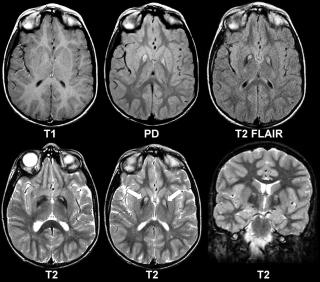

Особая диагностическая ценность МРТ коленного сустава состоит в получении исчерпывающей картины дегенеративно-дистрофических изменений (хронические артриты и остеоартрозы, повреждения суставных поверхностей) и возможности визуализации самых мелких травм (разрывы связок, сухожилий, переломы), визуализация хряща с последующим его картированием для определения дистрофических и травматических изменений.

Дистрофические изменения суставного хряща надколенника (с использованием опции «картирования хряща»)

МРТ помогает с большой точностью установить полный или же частичный разрыв мениска, прекрасно и наглядно отображает состояние связок коленного сустава. При диагностировании передней крестообразной связки МРТ показывает разрывы ясно и четко в 96%. Магнитно-резонансная томография наглядно демонстрирует не только разрывы сухожилий, но и гораздо более тонкие проблемы, возникающие во внутренней структуре, сопряженные с воспалением или рубцеванием тканей, которые при неблагоприятном прогнозе могут вызвать определенные хронические заболевания.